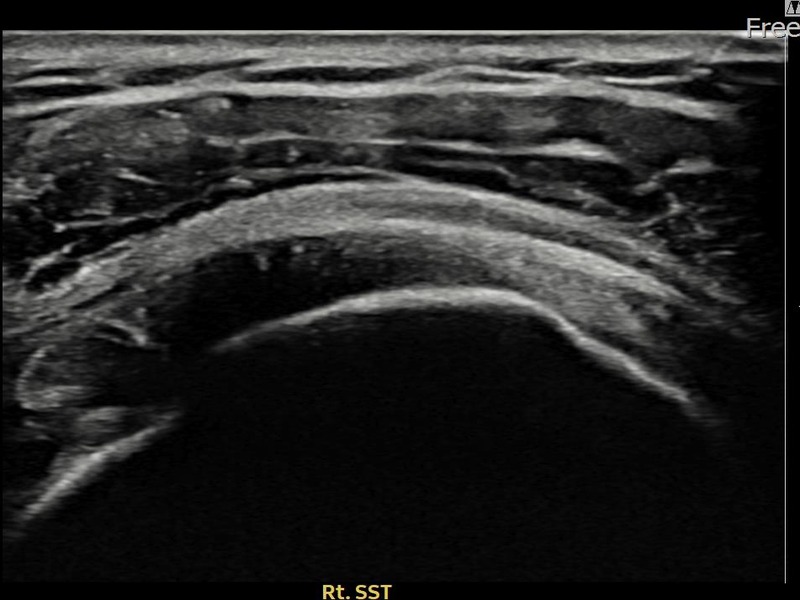

최ㅇㅇ님 · 우측 극상근건 관절면측 파열 진행형

우측 어깨 파열이 진행된 상태로 수술 없이 치료를 원해 내원하셨습니다. 다각도 초음파 평가 후 축소봉합술을 시행하여 힘줄 구조가 안정화되었습니다.

상세 보기 →